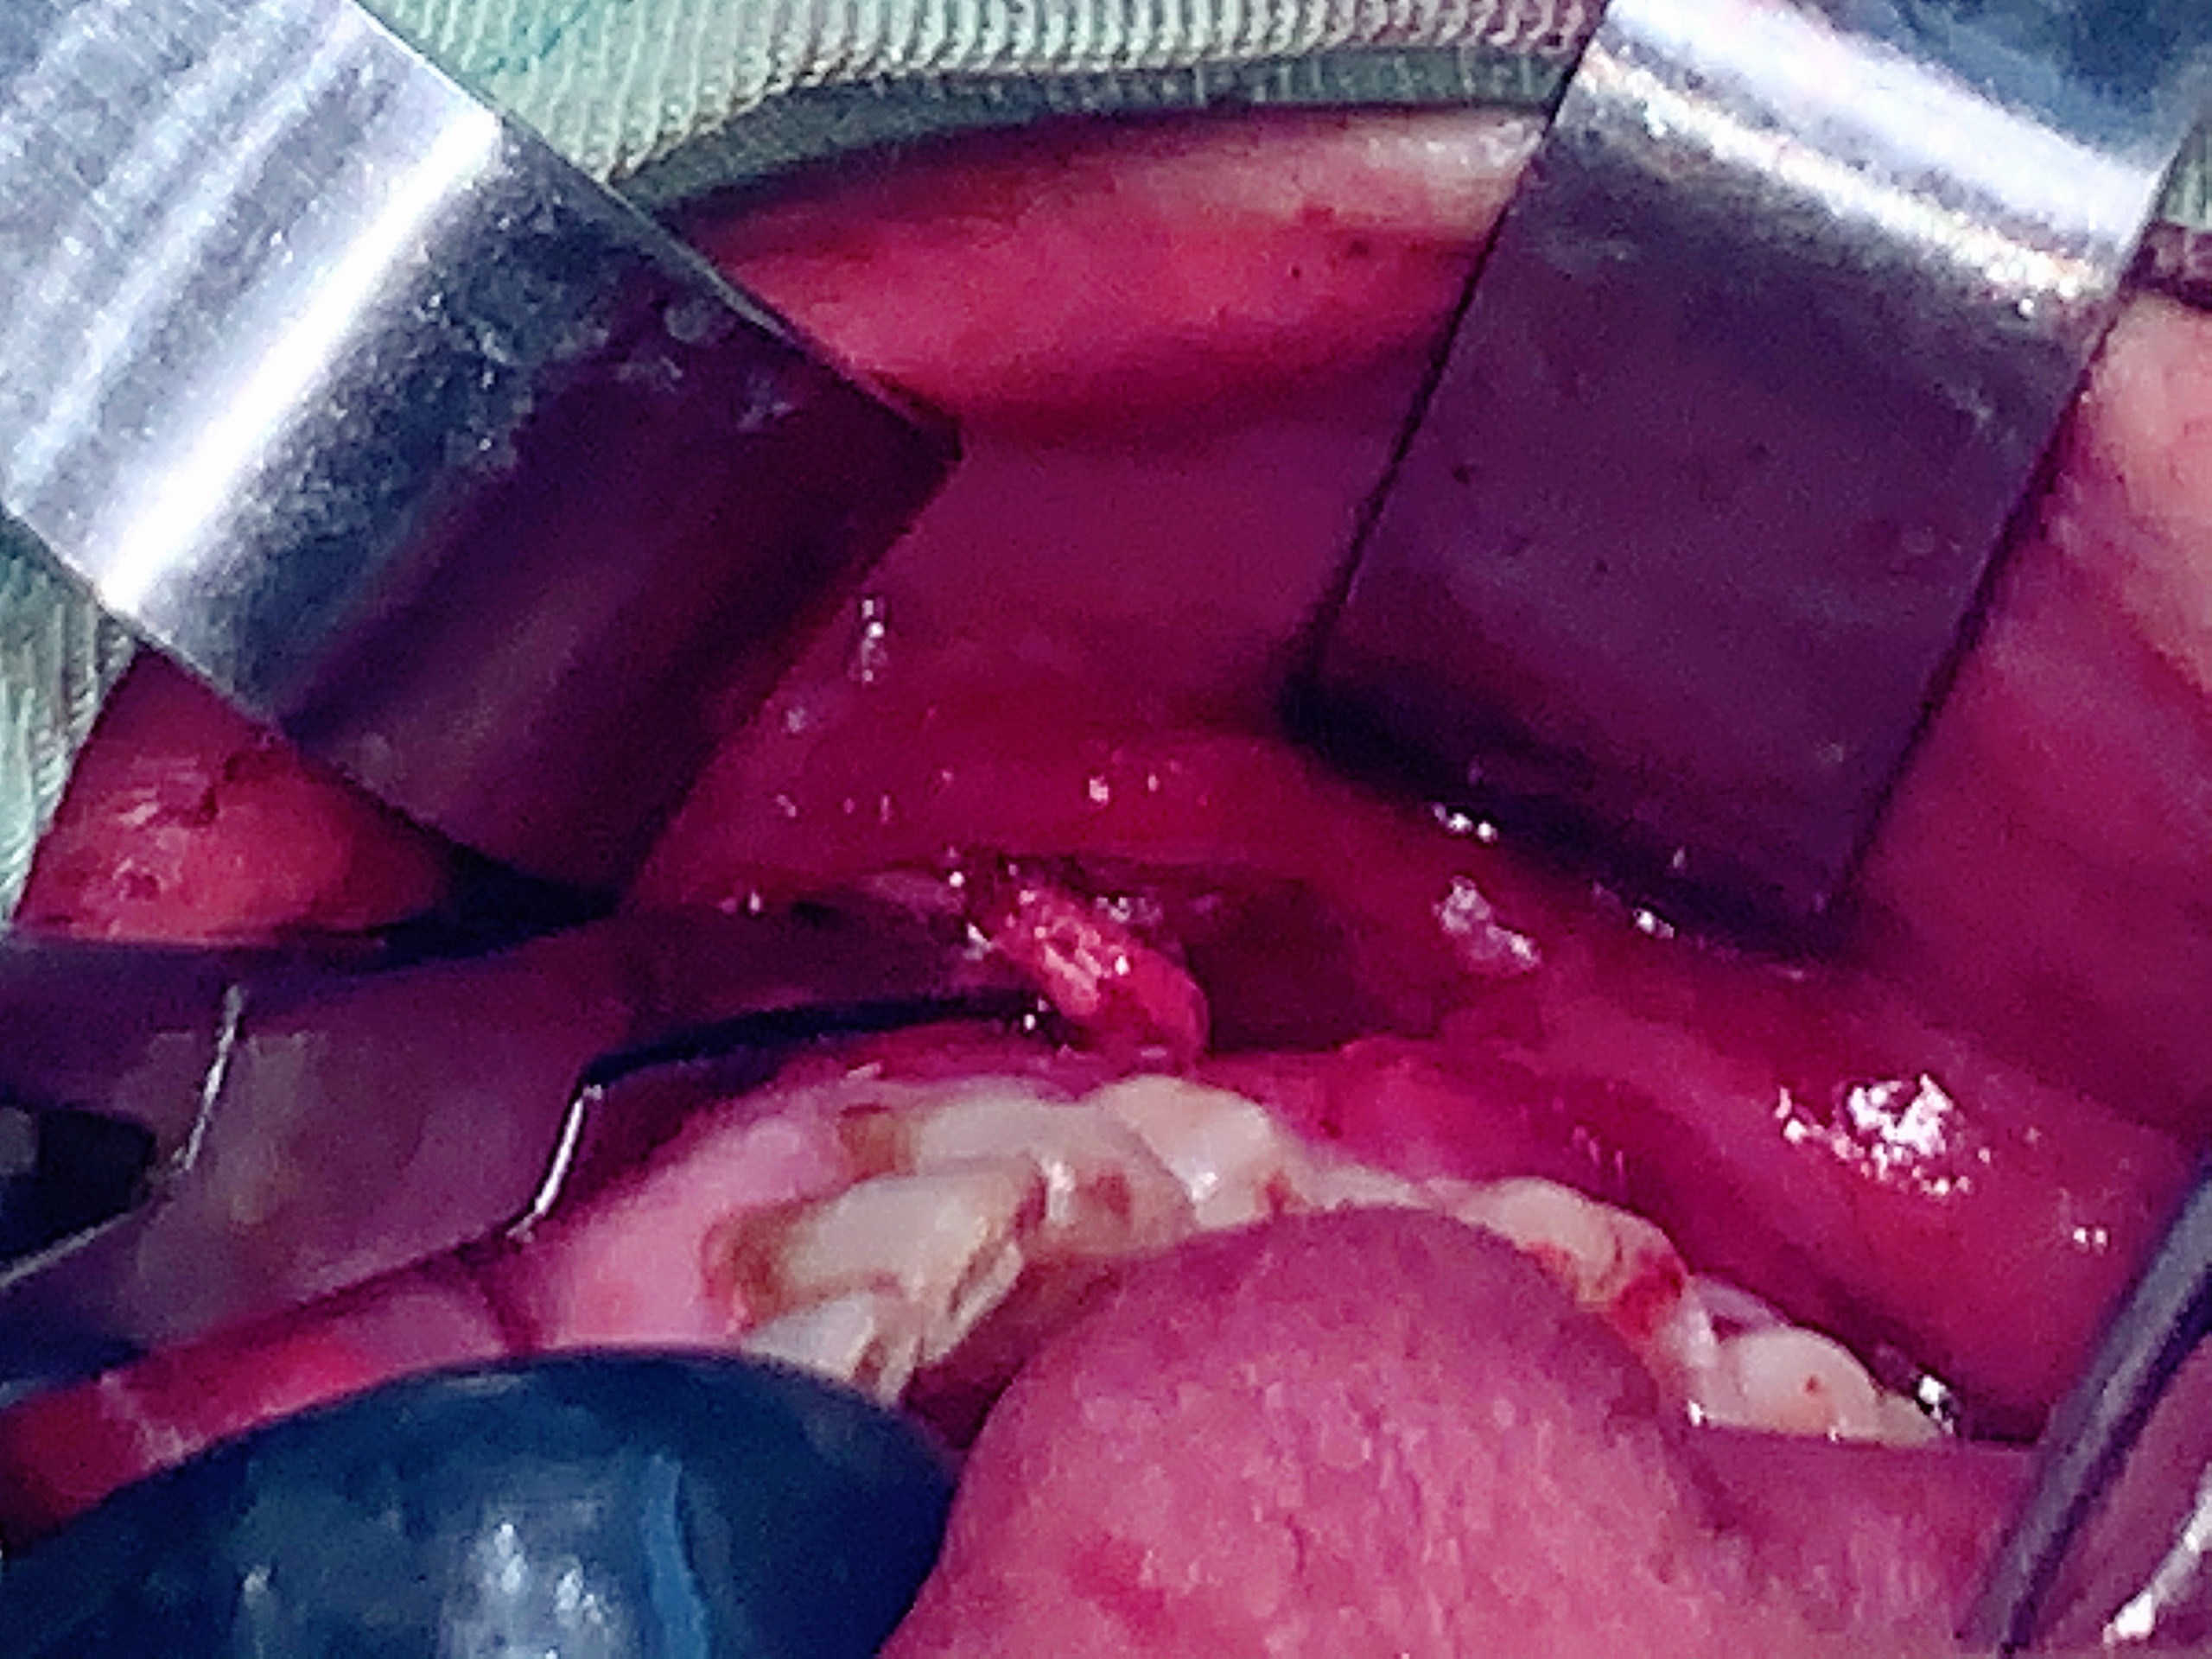

Trong quá trình phẫu thuật, bóc tách, nhận thấy khối u nằm sát thần kinh cằm, vị trí phức tạp, e kip bác sĩ Khoa Răng – Hàm – Mặt Bệnh viện Quốc tế Thái Nguyên đã tiến hành bóc tách bảo tồn thần kinh cằm và cắt bỏ khối u. Khối u sau khi cắt bỏ có kích thước 3x3cm. Kết quả giải phẫu bệnh là khối u mỡ lành tính. Sau 5 ngày hậu phẫu, hiện sức khỏe bệnh nhân đã ổn định và xuất viện.

Hình ảnh thần kinh cằm được bóc tách bảo tồn

Hình ảnh khối u mỡ kích thước 3×3 cm